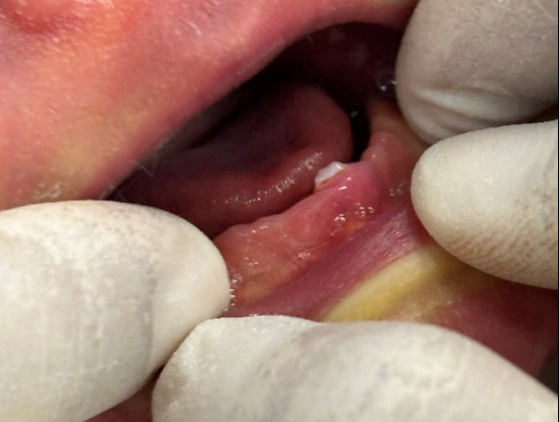

វេជ្ជបណ្ឌិតអាចព្យាបាលទារកដែលមានធ្មេញពីកំណើតក្នុងរយៈពេលមួយខែដំបូងបន្ទាប់ពីកំណើត - រូបថត: BSCC

ធ្មេញដែលរងផលប៉ះពាល់ពីកំណើតជារឿយៗខុសពីធ្មេញបឋមធម្មតា។ ពួកវាមានទំហំតូច រាងសាជី ពណ៌លឿង ឬពណ៌ត្នោតងងឹត ហើយមានផ្ទៃ enamel និង dentin ដែលមិនទាន់អភិវឌ្ឍ។ ឫសច្រើនតែខ្លីខ្លាំង ឬក៏អវត្តមាន ដែលធ្វើឱ្យធ្មេញរលុង។

ដោយផ្អែកលើកម្រិតនៃការផ្ទុះ មនុស្សត្រូវបានបែងចែកជា 4 ប្រភេទ៖ ប្រភេទទី 1 គឺជាធ្មេញដែលមានរូបរាងដូចសំបកស្តើង ជាប់នឹងអញ្ចាញធ្មេញ។ ប្រភេទទី 2 ជាប្រភេទធ្មេញរឹង ប៉ុន្តែនៅតែរលុង ព្រោះមិនមានឬសខ្លី។ ប្រភេទទី 3 គឺជាធ្មេញដែលទើបតែលេចចេញតាមអញ្ចាញធ្មេញ។ ហើយប្រភេទទី៤ គឺជាអញ្ចាញធ្មេញដែលហើម មានធ្មេញនៅខាងក្រោមមិនទាន់ផ្ទុះនៅឡើយ។ ក្នុងករណីភាគច្រើន ធ្មេញដែលផ្ទុះនៅពេលកើត គឺជាធ្មេញទារកធម្មតាដែលផ្ទុះដំបូង ប៉ុន្តែពួកគេក៏អាចជាធ្មេញលើសលេខផងដែរ។

ក្នុងពេលជាមួយគ្នានេះ ម្តាយក៏ជួបប្រទះការឈឺក្បាលសុដន់អំឡុងពេលបំបៅកូនផងដែរ។ ទីពីរ ធ្មេញមុតអាចប៉ះនឹងអណ្តាតរបស់ទារក ដែលបង្កឱ្យមានដំបៅលក្ខណៈដែលគេហៅថាជំងឺ Riga-Fede ។ នេះជាដំបៅរ៉ាំរ៉ៃ និងឈឺចាប់ដែលធ្វើឱ្យទារកមិនព្រមបៅដោះ និងខ្វះអាហារូបត្ថម្ភ។ ទី៣ ប្រសិនបើធ្មេញរលុងពេក មានហានិភ័យនៃធ្មេញជ្រុះ ហើយត្រូវលេប ឬស្រូបចូលតាមផ្លូវដង្ហើម។ ទោះបីជាមិនទាន់មានរបាយការណ៍ផ្លូវការជាច្រើនអំពីការថប់ដង្ហើមក៏ដោយ ទារកខ្លះត្រូវបានគេកត់ត្រាថាលេបធ្មេញ។